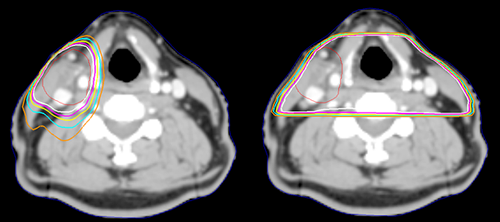

Which of the images above was most likely planned with IMRT